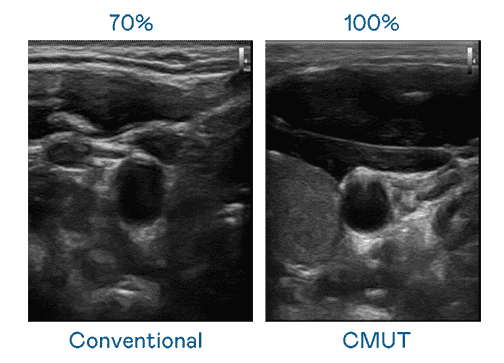

CMUT 技术是一种用电容式微机电元件来产生超音波讯号的技术。。。。与传统 PZT 压电式技术相比,,,CMUT 频宽增加 30%,,,更宽频的超音波讯号让影像解析度大幅提升,,是实现高影像品质医疗超音波扫描、、、促进精准医疗发展的关键技术。。。

大频宽带来超清晰影像

超音波影像的解析度高低,,,,首先取决于探头能发出的讯号频宽。。尊时凯龙 CMUT 可提供高清晰的超音波讯号,,,提供高频宽、、、高灵敏度、、、、影像纹理细节更高的超音波影像,,协助医护人员缩短影像判读时间及利用精准的医疗影像进行诊断。。。